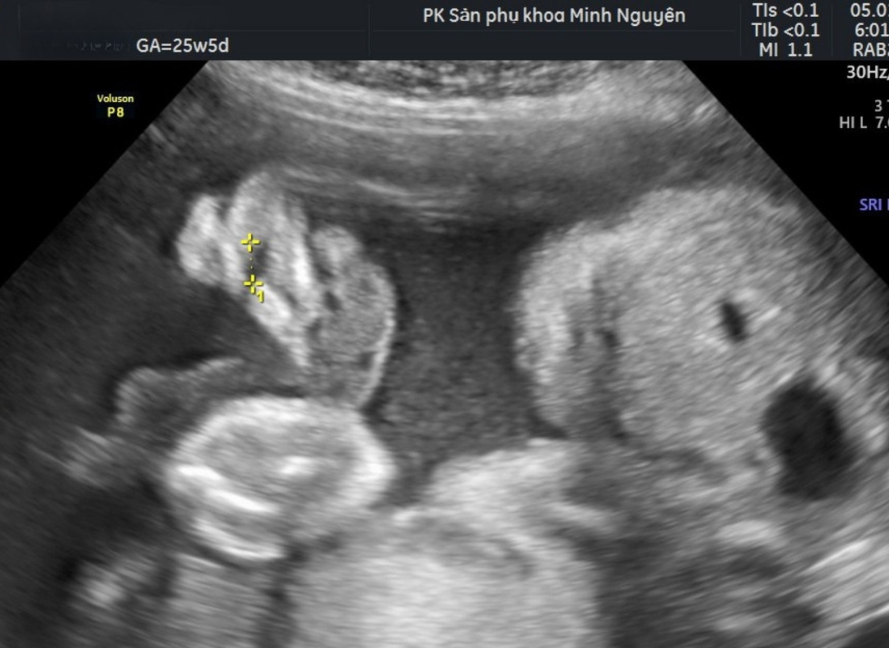

Chị H. đến phòng khám Dr Tú y học bào thai khi thai đã sang tuần 26. Trước đó một tuần, chị được thông báo trên siêu âm hình thái rằng thai có dấu hiệu sứt môi. Kết quả không kèm bất thường nào khác, nhưng chỉ một cụm từ đó cũng đủ khiến chị mất ngủ nhiều đêm.

Bác sĩ Tú không trả lời ngay. Bác sĩ mở lại hình ảnh siêu âm, xác nhận đây là nghi ngờ sứt môi đơn độc, không thấy dấu hiệu hở hàm ếch hay bất thường cơ quan khác, rồi mới bắt đầu giải thích từng bước.

Phát hiện sứt môi trên siêu âm có biết trước được khả năng phẫu thuật không?

Siêu âm thai chỉ đánh giá được hình thái, không đánh giá khả năng phẫu thuật hay kết quả thẩm mỹ sau này. Khi thấy sứt môi trên siêu âm, bác sĩ cần làm rõ các điểm sau:

• Sứt môi một bên hay hai bên

• Khe hở lớn hay nhỏ

• Có nghi ngờ hở hàm ếch kèm theo không

• Có bất thường nào khác đi kèm không

Nếu sứt môi là đơn độc, không kèm hở hàm ếch và không nằm trong hội chứng di truyền, thì khả năng phẫu thuật thành công sau sinh là rất cao.